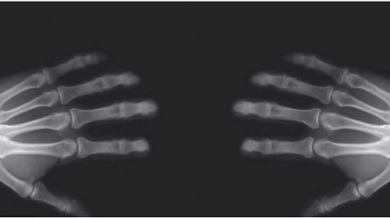

Se faire “craquer les doigts” est une habitude qu’ont de nombreuses personnes. Néanmoins, cela peut leur causer des problèmes au niveau des articulations, comme, par exemple, l’arthrite.

Les articulations sont le point où les os se retrouvent et s’unissent.

Toutes les articulations contiennent une zone appelée capsule articulaire. C’est une zone qui les protège et qui contient un lubrifiant naturel appelé liquide synovial. Ce lubrifiant est nécessaire pour le mouvement des articulations.

C’est précisément ce liquide qui influe sur le fameux “craquement” car il y a de l’air à l’intérieur de celui-ci. Au moment de croiser les jointures, l’articulation se sépare et élargit l’espace de l’intérieur de la capsule articulaire. Ceci entraîne ainsi les gaz dissouts à former des bulles pour occuper le nouvel espace créé.

En exerçant une force sur les jointures, les bulles formées s’échappent rapidement. Cela provoque par conséquent le son caractéristique des craquements.